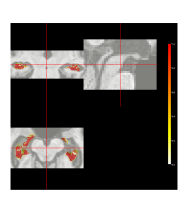

Figure 8 displays the posterior probability map for hippocampus inclusion, along with the point-wise standard deviations. The highest probabilities of inclusion are near the centers of the two regions. There is considerable uncertainty about the edges. If a researcher were only interested in the hippocampal volume for the patient, these probabilities could be used directly to estimate the volume, as discussed below.

One can threshold the posterior probabilities to obtain a binary inclusion map. After thresholding, we compare the resulting segmentation to those obtained by simple majority voting, globally-weighted majority voting, locally-weighted majority voting, and JLF. The global weighting is inversely proportional to each atlas’ average intensity difference from the target. Local weighting is done similarly using voxel-specific intensity differences. Figure 9 displays one slice of the manual segmentation along with that which is obtained by thresholding the posterior inclusion probabilities at 0.5. The hippocampus is a relatively small structure compared to the full three-dimensional image (as can be seen in, e.g., Supplementary Figure 4). In this case, Taha and Hanbury (2015) argue that the Dice coefficient defined in Section 3 is not the best measure for evaluating a segmentation. However, the volume of the hippocampus is important for volumetry in the study of AD progression. Thus, we follow the suggestion of Taha and Hanbury (2015) and use the volume similarity as an evaluative metric, defined as , where and denote false negatives, false positives, and true positives, respectively. Bayesian label fusion attains . This is competitive with JLF, the current state-of-the-art (), and superior to both simple and weighted voting procedures. (VS values are displayed in Figure 9.)